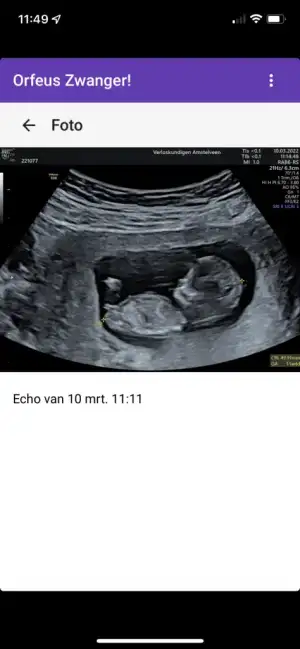

Bizde kontrolden geldik . 11+4 çıktı . Önde gidiyoruz 3 gün. Doğum da 25 Eylül tahmini tabi:) kıpırdanıyordu eli havada.. herşey güzel görünüyor dedi.

Bizde kontrolden geldik . 11+4 çıktı . Önde gidiyoruz 3 gün. Doğum da 25 Eylül tahmini tabi:) kıpırdanıyordu eli havada.. herşey güzel görünüyor dedi.

Resimimiz de ekteki gibi :)Selam kızlar ,

Bizde kontrolden geldik . 11+4 çıktı . Önde gidiyoruz 3 gün. Doğum da 25 Eylül tahmini tabi:) kıpırdanıyordu eli havada.. herşey güzel görünüyor dedi.

Ayy maşallah nub teorisine göre erkek gibi gözüküyor sizinkiResimimiz de ekteki gibi :)